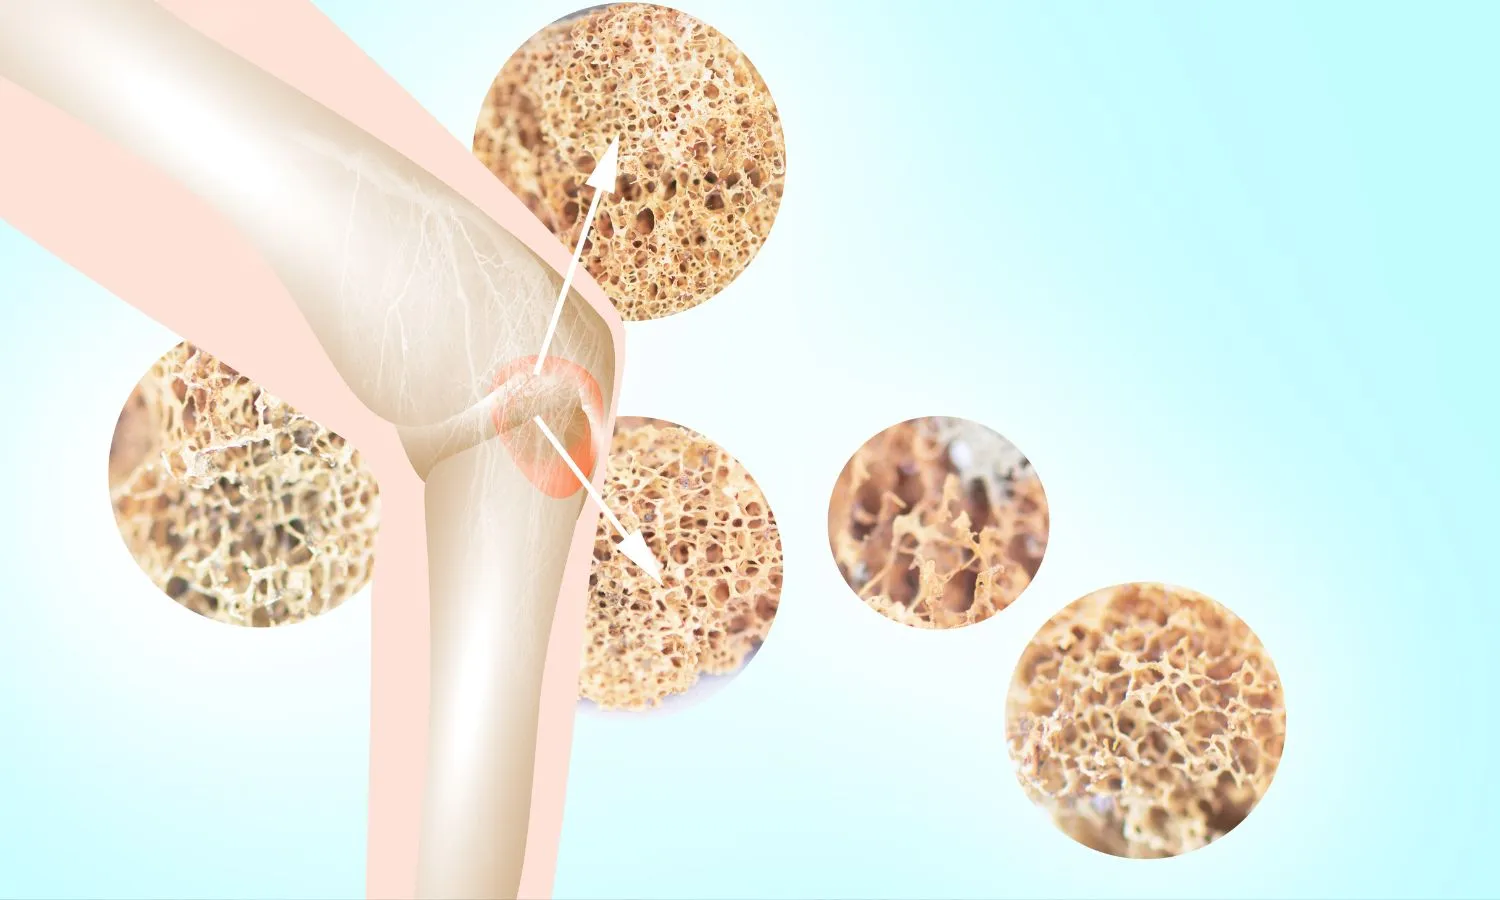

Osteoporosis

Osteoporosis is a common bone disease characterized by low bone mass and deterioration of bone tissue.